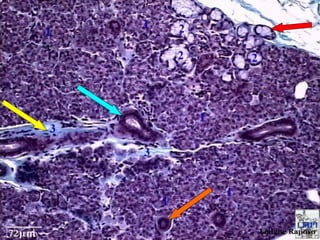

Monitoria de Histologia II

•   Qual o corte histológico?

•   Qual a estrutura apontada pela seta amarela?

•   Qual a estrutura apontada pela seta vermelha?

•   Qual a estrutura apontada pela seta azul?

•   Qual a estrutura apontada pela seta verde?

•   Qual a estrutura apontada pela seta laranja?